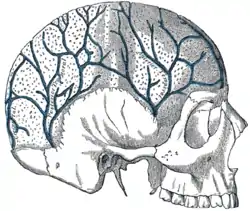

The calvaria is the top part of the skull. It is the superior part of the neurocranium and covers the cranial cavity containing the brain. It forms the main component of the skull roof.

The calvaria is made up of the superior portions of the frontal bone, occipital bone, and parietal bones.[1] In the human skull, the sutures between the bones normally remain flexible during the first few years of postnatal development, and fontanelles are palpable. Premature complete ossification of these sutures is called craniosynostosis.

The outer surface of the skull possesses a number of landmarks. The point at which the frontal bone and the two parietal bones meet is known as the bregma. The point at which the two parietal bones and the occipital bone meet is known as the lambda. Not only do these landmarks indicate the fontanelle in newborns, they also act as reference points in medicine and surgery.

The inner surface of the skull-cap is concave and presents depressions for the convolutions of the cerebrum, together with numerous furrows for the lodgement of branches of the meningeal vessels. Along the middle line is a longitudinal groove, narrow in front, where it commences at the frontal crest, but broader behind; it lodges the superior sagittal sinus, and its margins afford attachment to the falx cerebri. On either side of it are several depressions for the arachnoid granulations, and at its back part, the openings of the parietal foramina when these are present.

It is crossed in front by the coronal suture and behind by the lambdoid suture, while the sagittal suture lies in the medial plane between the parietal bones.

Most bones of the calvaria consist of internal and external tables or layers of compact bone, separated by diploë. The diploë is cancellous bone containing red bone marrow during life, through which run canals formed by diploic veins. The diploë in a dried calvaria is not red because the protein was removed during preparation of the cranium. The internal table of bone is thinner than the external table, and in some areas there is only a thin plate of compact bone with no diploë.[2] Calvarial bones are supplied by endosteal and periosteal sheaths which are innervated by the nociceptors, sensory, sympathetic, and parasympathetic nerves. Horizontal section of the mouse pups showed that the density of nerve fibers was highest in the region of forehead, temples, and the back of head which crossing the frontal, parietal, and interparietal bones. In the calvarial innervation in the adult mouse, CGRP-labeled fibers and peripherin were seen in the sutures, emissary canals, and bone marrow but not in diploe. Nerve fibers passing through the emissary canals and cavity of bone marrow provided the branches of periosteal and dural nerves whereas fibers from the sutures gave out to the dural nerves.[3]